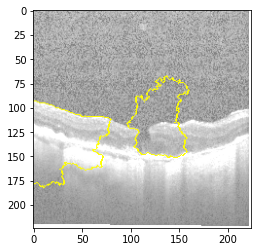

Fig 6, 7, 8 and 9 depicts the visualization of correct predictions by our proposed CNN model where fig 6 is class CNV, fig 8 is class DME, fig 7 is DRUSEN and finally, fig 9 is NORMAL. Here the first photo in every class is the original image. The LIME map of our suggested model’s prediction is shown in image B whereas in image C the positive region is highlighted in specific sections on the original image. For Image D we have increased the number of features from 5 to 10 thus more regions have been predicted as the positive region which is highlighted in green. After increasing the features from 5 to 10, some of the regions are predicted wrongly. The red regions represent the output of incorrect prediction. The following image represents the Grad-CAM heatmap highlighting the regions with our model’s prediction.